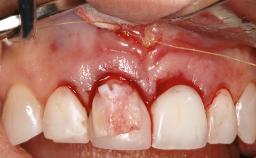

Reconstructive Surgical Treatment of Peri-Implantitis with Long-Term Follow-up

A 72-year-old female patient was referred to the specialist clinic with signs of peri-implantitis associated with implant 14. Two implants (sites 14 and 15) had been in function for three years. The patient was in good general health and was not taking any medication. She was a former smoker (12–15 cigarettes a day for 50 years) but had ceased smoking two years prior to implant placement. Her periodontal condition was stable, with no probing depths above 5 mm and a full-mouth plaque score (FMPS) of 35%.